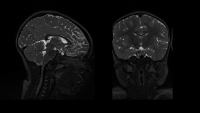

While using MRI to study the brain activity of children with ADHD, Columbia researcher Claudia Lugo-Candelas was struck by the fact that children as young as two or three were already having behavioral and emotional difficulties. She's now investigating if those difficulties may get primed in utero. Image provided by Claudia Lugo-Candelas.

Lugo-Candelas was interested in better understanding the roots of self-regulation; why did some children struggle with it so much? She began a postdoctoral research fellowship at Columbia in 2019, using MRI scans to study the brain activity of children with ADHD. She was struck by the fact that children as young as two or three were already having behavioral and emotional difficulties.